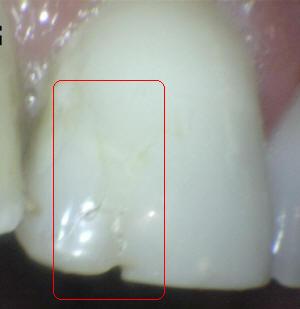

Sistema Internacional para la Detección y Evaluación de Caries (ICDAS)

¿Determine los códigos pertinentes a cada imagen?

Click en el hipervínculo: Para comparar el resultado de su diagnóstico